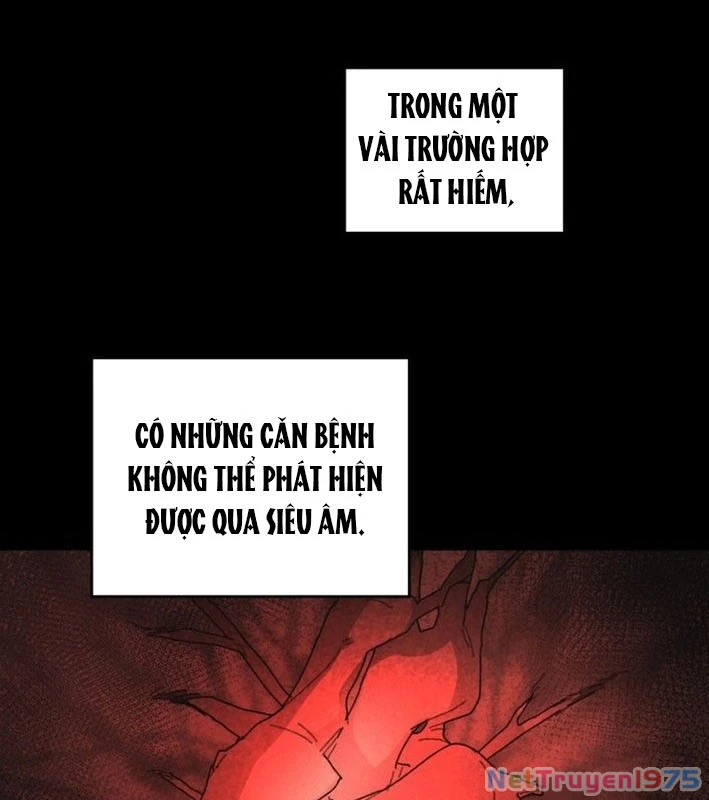

Kẻ Chôn Cất Quái Vật - Chapter 1